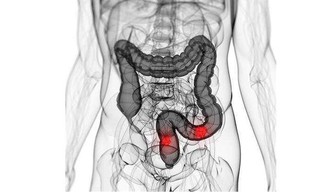

3.晨起排便

人晚上睡覺,腸道和胃其實是並沒有休息,還是在不停的蠕動,早上的時候腸道中就已經積累了很多的垃圾了,這時候排便,很容易就能將身體中的毒素排出來,減輕腸道的負擔,腸道暢通才是真正減輕了人體的負荷,緩解便秘。便秘可引起肛腸疾患、胃腸功能紊亂或誘發心、腦血管疾病。積極預防和治療便秘,腸胃才會更健康。